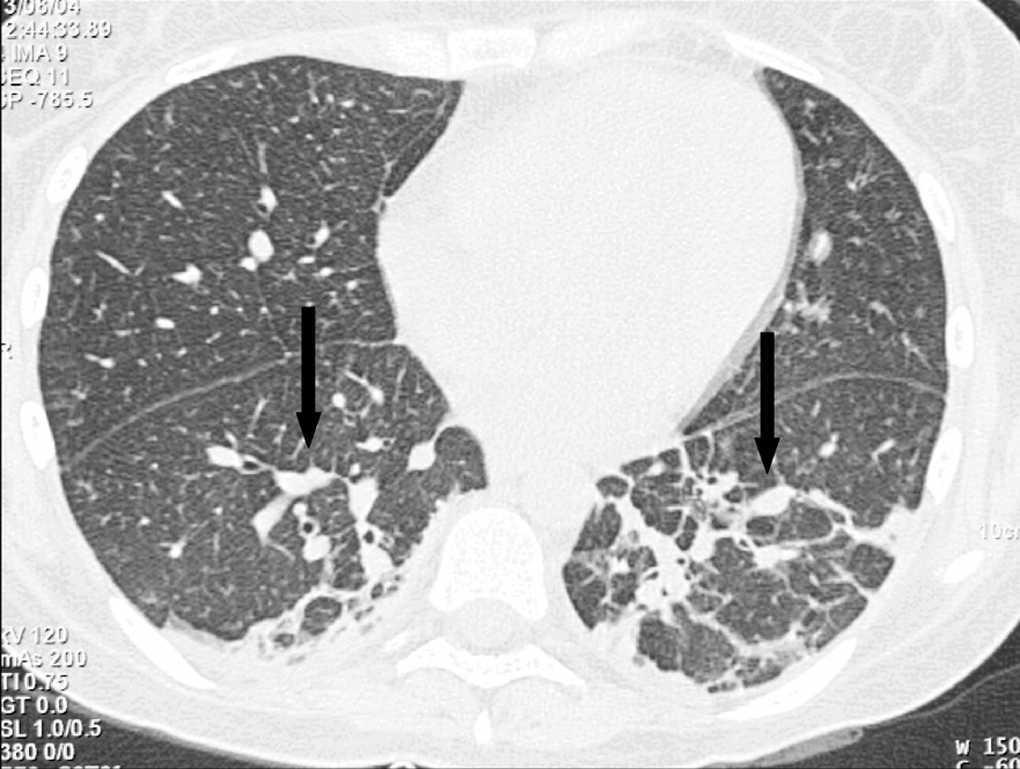

Mujer de 31 años, que ingresa por shock séptico aislándose en dos hemocultivos Staphylococcus aureus en paciente con neutropenia febril de 5 días de evolución tras ciclo de consolidación de linfoma no Hodgkin B, por lo que recibió tratamiento antibiótico empírico en un primer momento con vancomicina e imipenem y posteriormente dirigido con cloxacilina y la retirada del catéter de Hickman, cuyo cultivo semicuantitativo fue negativo. No precisó ventilación mecánica. La radiografía (Rx) de tórax fue normal. Al no encontrar foco evidente de infección se realiza tomografía axial computarizada (TAC) torácica a su ingreso que muestra mínimos cambios consistentes en engrosamiento discretamente irregular de los septos interlobulillares de ambos lóbulos inferiores en su porción posterior, diagnosticándose de neumonía (fig. 1; flechas negras). La paciente evoluciona de forma satisfactoria, desapareciendo la fiebre, pudiéndose retirar los inotrópicos y vasopresores y mejorando la relación PaO2/FiO2; recupera la neutropenia a los 10 días de ingreso en que se realiza TAC de control que confirma consolidación alveolar bilateral (fig. 2; flechas blancas).

Figura 1